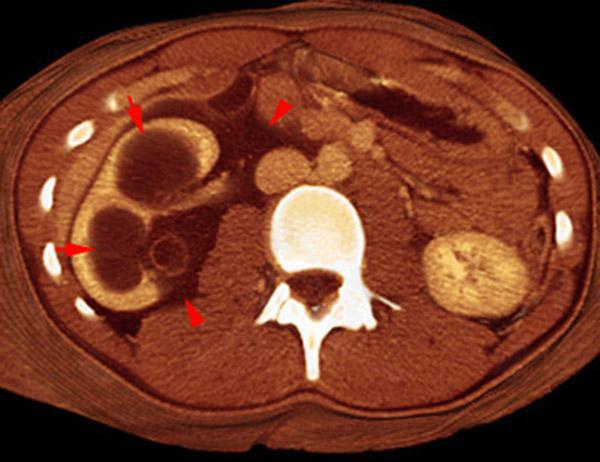

VR seccional. Visión axial caudal. TC contrastado en fase venosa. Varón de 18 años con traumatismo abdominal. Nefromegalia derecha. Hidronefrosis (flechas) con presencia de líquido en los espacios pararrenal anterior y perirrenal (puntas de flecha)